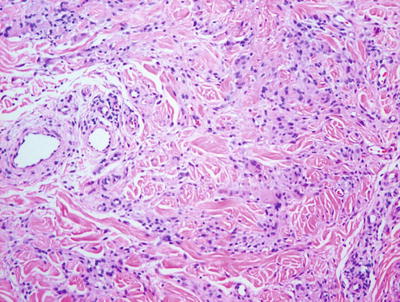

Nonallergic foreign body granulomas demonstrate an admixture of lymphocytes, histiocytes, multinucleated giant cells and, in early lesions, clusters of neutrophils [2, 3] (Fig. 6.1). The most common foreign material that elicits this type of reaction within the skin is keratin , often secondary to a ruptured folliculitis. The keratin is often readily identified within multinucleated giant cells. Other materials may be similarly located and can be visualized with routine microscopy or in some cases highlighted with light polarization (Fig. 6.2). Foci of necrosis are often seen centrally and surrounded by the granulomatous reaction. Changes within the overlying epidermis are related to route of entry of the foreign material into the dermis , and may display ulceration or epidermal acanthosis if the material has been present for a period of time and caused secondary local trauma from rubbing.

Fig. 6.1

A dense granulomatous infiltrate characterized by multinucleated giant cells and a mixed inflammatory infiltrate is seen in foreign body type granulomas. Foreign material can be apparent on routine H&E sections